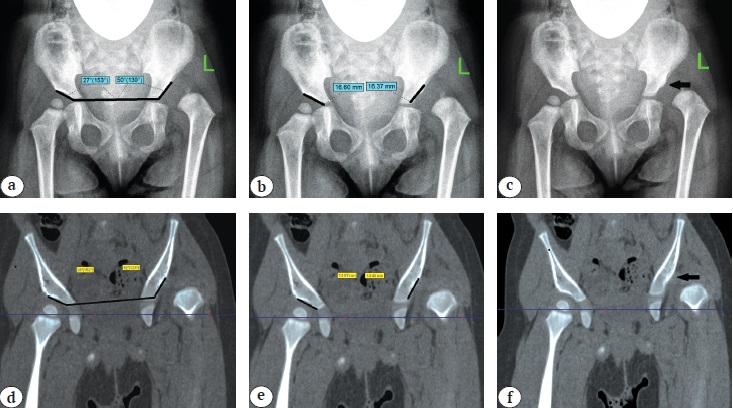

In order to objectify the data, the above-mentioned criteria were calculated using both X-rays and CT slice in the middle of the acetabulum (Figs. 1, 2).

Fig. 2. Determination in patients with Tönnis grade IV DDH based on X-ray and CT results: a, d — acetabular index; b, e — length of acetabulum arch; c, f — absence of bone oriel (indicated by black arrow)